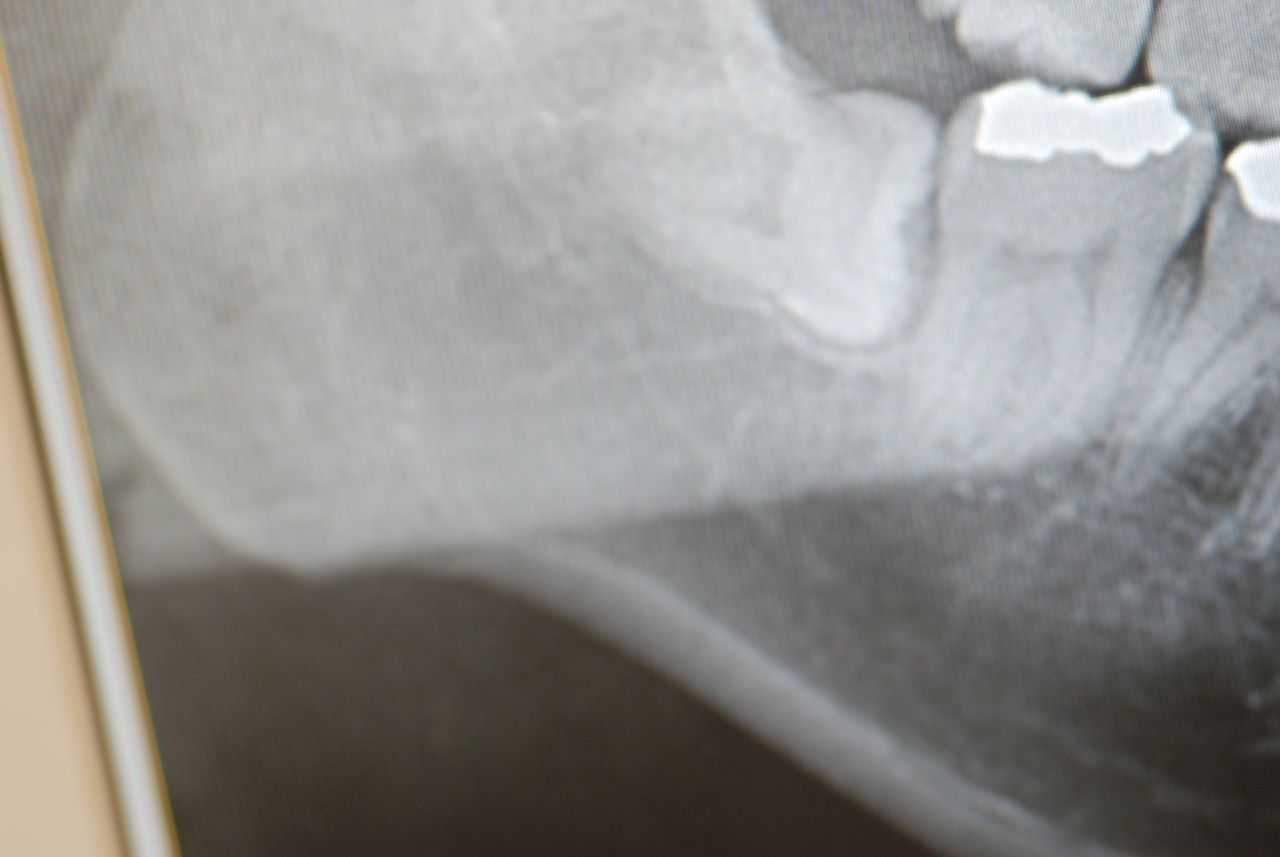

2、67才、女性、主訴は噛みあわせがおかしい。

矯正している。左の上下の6才大臼歯を保険の金属冠から都内の某所でジルコニアという硬いセラミック?冠に変えてからおかしくなっていったそうです。担当の歯科医師は削ったりしてどちらの歯も当たっていないぐらい削っているに違和感が取れないという主訴です。兵庫県の先生からの相談でした。